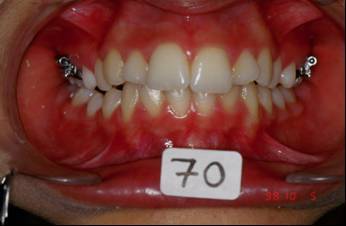

Voici les photos intermediaire apres: un QH, reeducation,propuleur Balters simple, multi-bague avec el II ancrage maxi bas, mini haut avec le trace. La maman et la patiente n'etaient pas d'accord du tout! Je comprends tout a fait leur point de vue... A suivre

Picture1 pvviml - Eugenol

Picture2 ghm9hp - Eugenol

Picture3 yvnauf - Eugenol

Picture4 pk0wos - Eugenol